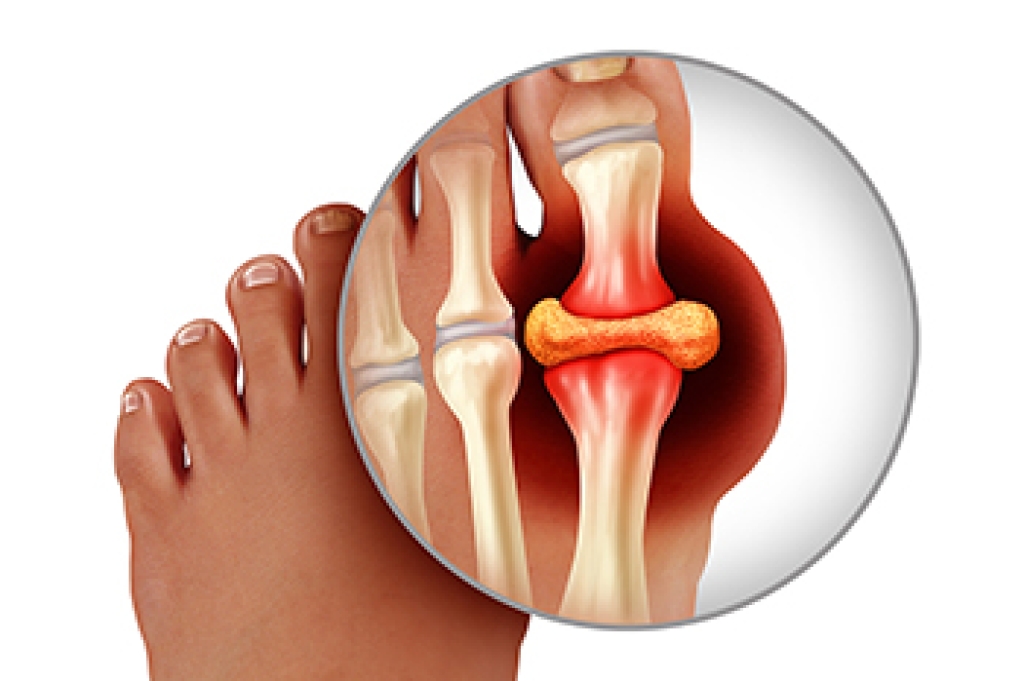

Gout, a complex form of arthritis, is often accompanied by intense pain and inflammation that targets the joints, including the feet. This condition results from the accumulation of uric acid crystals in the joints, leading to sudden and excruciating attacks of pain. The underlying cause is often an overproduction or inefficient excretion of uric acid, which is a waste product. Dietary factors, such as high purine foods and excessive alcohol consumption, can exacerbate gout. Managing gout involves implementing various treatment methods. Medications may help to reduce pain and inflammation during attacks, while long term strategies focus on lowering uric acid levels. This can be accomplished through lifestyle adjustments and prescribed medications. Consulting a podiatrist is paramount in tailoring an effective treatment plan. If you are afflicted with gout, it is strongly suggested that you are under the care of this type of doctor who can effectively help you to manage this condition.

Gout is a type of arthritis caused by a buildup of uric acid in the bloodstream. It often develops in the foot, especially the big toe area, although it can manifest in other parts of the body as well. Gout can make walking and standing very painful and is especially common in diabetics and the obese.

Gout can easily be identified by redness and inflammation of the big toe and the surrounding areas of the foot. Other symptoms include extreme fatigue, joint pain, and running high fevers. Sometimes corticosteroid drugs can be prescribed to treat gout, but the best way to combat this disease is to get more exercise and eat a better diet.